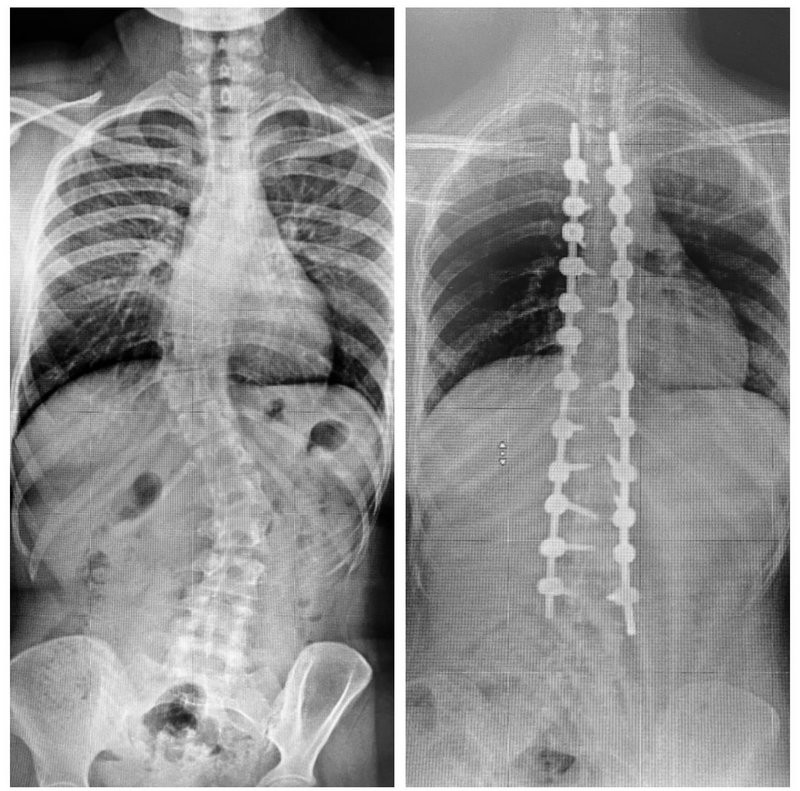

أنهى فريق طبي بمستشفى الدكتور سليمان الحبيب بالقصيم، معاناة شابة تبلغ من العمر 18 سنة، كانت تعاني من انحراف خلقي مضاعف في العمود الفقري "الجنف"؛ الأمر الذي تسبب في تأجيل المريضة لدراستها.. هذا ما أوضحه الدكتور هاني الجهني استشاري جراحة المخ والأعصاب والعمود الفقري الحاصل على البورد الفرنسي ورئيس الفريق الطبي المعالج.

وأضاف أن المريضة وصلت للمستشفى برفقة ذويها تشكو من انحناء حاد في العمود الفقري، يصاحبه آلام حادة ومتكررة مع صعوبة التبول، بالإضافة إلى مشاكل دائمة في التنفس؛ مشيرًا إلى أنه تم إخضاع المريضة لكل التحاليل المخبرية وفحوصات دقيقة بالرنين المغناطيسي (M.R.I) والتصوير المقطعي (C.T Scan)، وقد أبانت الفحوصات أن وضع المريضة يعد من الحالات المعقدة جدًّا، نظرًا لوجود اعوجاجين؛ الأول ناحية الصدر نسبته 55 درجة، أما الانحراف الثاني أسفل الظهر بنسبة 40 درجة.

وعن العملية أفاد استشاري جراحة المخ والأعصاب والعمود الفقري بأن الفريق الطبي المعالج قرر التدخل الجراحي بعد مراجعة دقيقة لكل المعطيات الطبية، موضحًا أن العملية استغرقت 6 ساعات متواصلة، وتم فيها تعديل الانحرافين بنجاح تام عبر استخدام أحدث التقنيات وأدوات تثبيت الفقرات والمصنّعة من مادة التيتانيوم والكوبلت.

وقال الدكتور "الجهني": إن جهود الفريق الطبي والتقنيات الحديثة المستخدمة ساهما في إنجاح العملية بنسبة 100%، مضيفًا أن المريضة استطاعت في اليوم الثاني بعد العملية الجراحية، الوقوف والمشي ولله الحمد، وخرجت من المستشفى في غضون 5 أيام وهي بصحة جيدة.